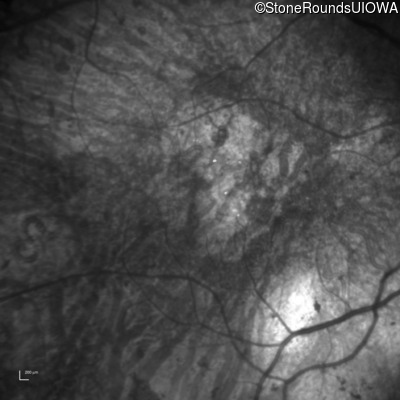

Type 2 Usher Syndrome (IB1b)

Age at visit:

76 years

OD

OS

1/200 sc

Type 2 Usher Syndrome

ARSG

Arg95Gln CGG>CAG

Ala234 ins1gC

AR